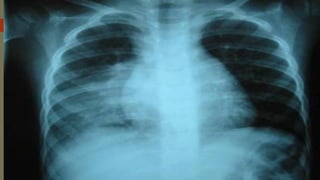

La neumonía intrahospitalaria se presenta en las 48-72 horas después del ingreso al hospital y es causada por patógenos comunes en entornos hospitalarios como bacterias, hongos y virus. Los pacientes más propensos son aquellos con enfermedades subyacentes graves o que requieren ventilación mecánica. El diagnóstico se realiza mediante exámenes radiológicos y de laboratorio, y el tratamiento inicial suele ser empírico con antibióticos que consideren la flora bacteriana y resistencias del hospital.